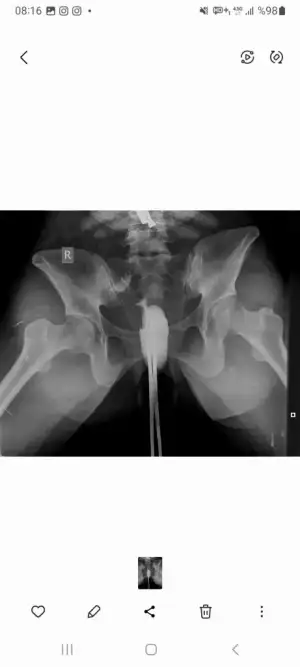

Canım sol üst köşede sağda olmayan bir beyazlık var tek farklılık orayı görüyorum benMerhaba bayanlar Hsg çektirdim siz anlıyor musunuz filmden kendi doktorumla henüz görüşemedim. 2 yildir bebek.istiyorum olmuyor. Yorumlarınızı paylaşırsanız sevinirim

Çok korkuyorum Tüplerde tıkanıklık ya da başka bi sorun çıkacak diyeCanım sol üst köşede sağda olmayan bir beyazlık var tek farklılık orayı görüyorum ben

Benimmdoktorum çeker çekmez bilgilendirdi beni sizi neden bilgilendirmediler acabaÇok korkuyorum Tüplerde tıkanıklık ya da başka bi sorun çıkacak diye